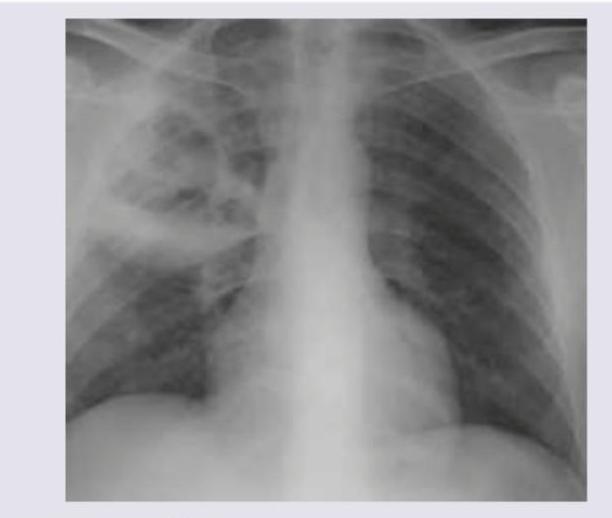

A 45-year-old alcoholic presents with severe respiratory distress and red current jelly sputum. On examination bronchial breathing was heard in right infraclavicular and inframammary areas. The X-ray chest is shown below. All are correct about the organism incriminated except:

Explanation: The clinical presentation of an alcoholic with **severe respiratory distress** and **red currant jelly sputum** is pathognomonic for pneumonia caused by ***Klebsiella pneumoniae***. The chest X-ray showing consolidation in the right upper lobe further supports this diagnosis. The question asks which statement is **INCORRECT** (except) regarding *Klebsiella pneumoniae*. ***Indole positive*** - *Klebsiella pneumoniae* is **indole negative**, not indole positive. This is the incorrect statement. - The indole test detects the production of indole from tryptophan metabolism. *K. pneumoniae* does not produce indole, which differentiates it from *Escherichia coli* (indole positive). - This is a key biochemical differentiator in the Enterobacteriaceae family. *Urease positive* - *Klebsiella pneumoniae* is **urease positive**. This is a correct statement. - Urease production is a characteristic feature used in biochemical identification. - The enzyme hydrolyzes urea to ammonia and carbon dioxide. *Citrate positive* - *Klebsiella pneumoniae* is **citrate positive**. This is a correct statement. - It can utilize citrate as its sole carbon source, demonstrated by the Simmons citrate test. - This is part of the IMViC testing panel. *Voges-Proskauer positive* - *Klebsiella pneumoniae* is **Voges-Proskauer positive**. This is a correct statement. - The VP test detects acetoin production during glucose fermentation. - The standard IMViC profile for *K. pneumoniae* is: Indole (-), Methyl Red (-), Voges-Proskauer (+), Citrate (+). **Key Point:** *Klebsiella pneumoniae* is indole negative, which is the most important biochemical feature distinguishing it from *E. coli* in clinical microbiology.